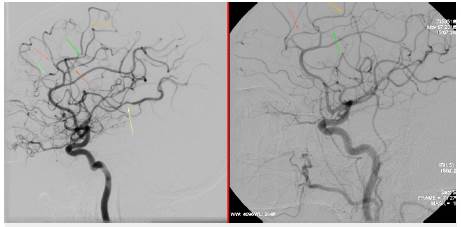

Mujer de 58 años de edad, ama de casa, ingresó por 15 días de evolución de cefalea de inicio hiperagudo pulsátil, en región occipital propagada a región frontal derecha, periorbitaria y nasal, intensidad 9/10, asociado a múltiples emesis, fosfenos y parestesias en manos. Había intensificación con la maniobra de Valsalva, no fue precedida de aura y no tuvo alteración de la conciencia u otro síntoma adicional. Los síntomas se presentaron durante una sesión de masaje en un spa, la paciente relató que en un momento le indicaron que realizara maniobras de Valsalva repetidamente y durante este periodo de tiempo se instaura la cefalea. Como antecedentes, tiene hipertensión arterial y dislipidemia en tratamiento con losartan 50 mg cada día y atorvastatina 40 mg cada noche, negaba abuso de alcohol o de tabaco, y una hija falleció por hemorragia subaracnoidea aneurismática 10 meses atrás. Se encontró deshidratada, con presión arterial 170/80 mmHg, frecuencia cardiaca 82/min; frecuencia respiratoria 20/ min; saturación de oxígeno 92% al ambiente. Talla 1,65 m, peso 78 kg, IMC 28 kg/m2, sin anormalidad en su exámen físico general. En el fondo de ojo se observaron arterias en hilo de cobre bilateral sin papiledema, no tuvo signos de irritación meníngea, no hubo alteración de otros pares craneanos ni de la fuerza o sensibilidad o coordinación. La resonancia cerebral simple mostró sangre en el espacio subaracnoideo de la cisura interhemisférica (Figura 1); dado esto y por el antecedente de la hija, se propuso practicar una panagiografía cerebral. Se trasladó a la unidad de cuidados intermedios y se inició terapia con nimodipino 60 mg cada 4 horas; no presentó deterioro neurológico y el seguimiento con doppler transcraneal no mostró signos de vasoespasmo. En la panangiografía cerebral no se identificaron aneurismas ni malformaciones arteriovenosas o fístulas, sin embargo, en arterias de mediano y pequeño calibre tanto en territorio anterior como posterior se evidenciaron múltiples estenosis y dilataciones segmentarias generando la imagen de "salchichas atadas" (Figuras 2 a 4). Se hizo la solicitud de perfil autoinmune para evaluar dentro del diagnóstico diferencial vasculitis sistémica, los resultados de los anticuerpos fueron: factor reumatoide negativo, C3 146 (normal), C4 28,7 (normal), anticuerpos antimieloperoxidasa negativos, anticuerpos antiproteinasa 3 negativos, anticuerpos antinucleares negativos.

Figura 2: Arteriografía de la carótida interna izquierda. Se observa estenosis y dilataciones segmentarias de ramas de las arterias cerebrales anterior y media (ver flechas).

Figura 3: Arteriografía de la carótida interna derecha. A la izquierda el estudio inicial muestra constricción arterial segmentaria (signo de "salchichas atadas") en ramas de las arterias cerebrales anterior y media. A la derecha el estudio control a los 3 meses muestra normalización de los hallazgos (ver flechas).